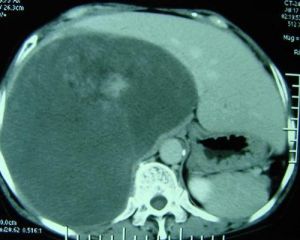

2.CT 表現為邊緣清晰的低密度區CT值小,可達-90Hu以上,是肝內腫瘤CT值最低的,注射造影劑後無增強反應。

在影像檢查方面肝脂肪肉瘤與肝脂肪瘤難以區分。